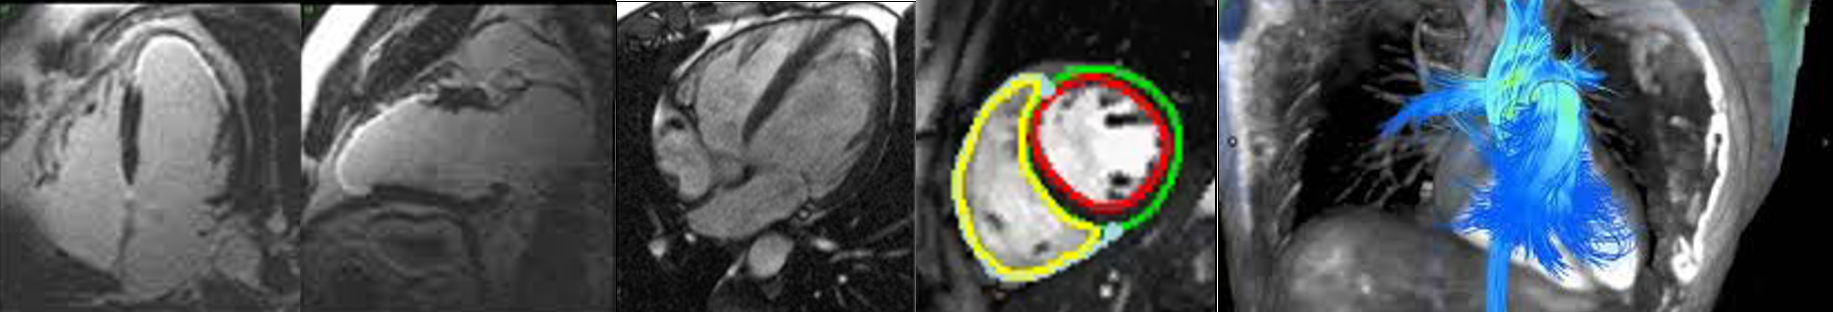

Refer to caption

Figure 1: Examples of Cardiac magnetic resonance (CMR) images. CMR comprises hundreds of images of differing views and image types, the large majority of which do not contain an indication of pathology. The corresponding report is an analysis of all these images, resulting in difficulty in aligning images with text reports.